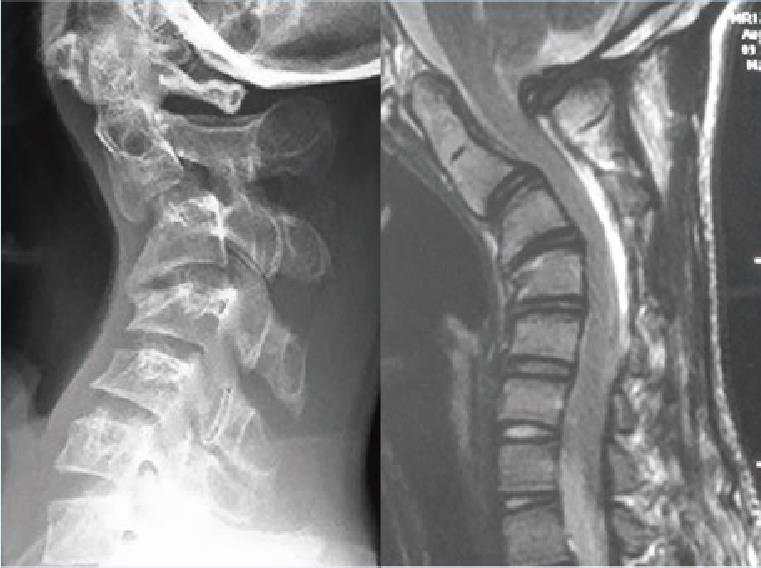

病例3:颈后路保留后方肌肉韧带复合体的单开门椎管扩大成形术

脊髓型颈椎病,术前X线和核磁示多节段椎间盘突出

颈后路保留后方肌肉韧带复合体的单开门椎管扩大成形术,术后随访示椎管扩大良好。